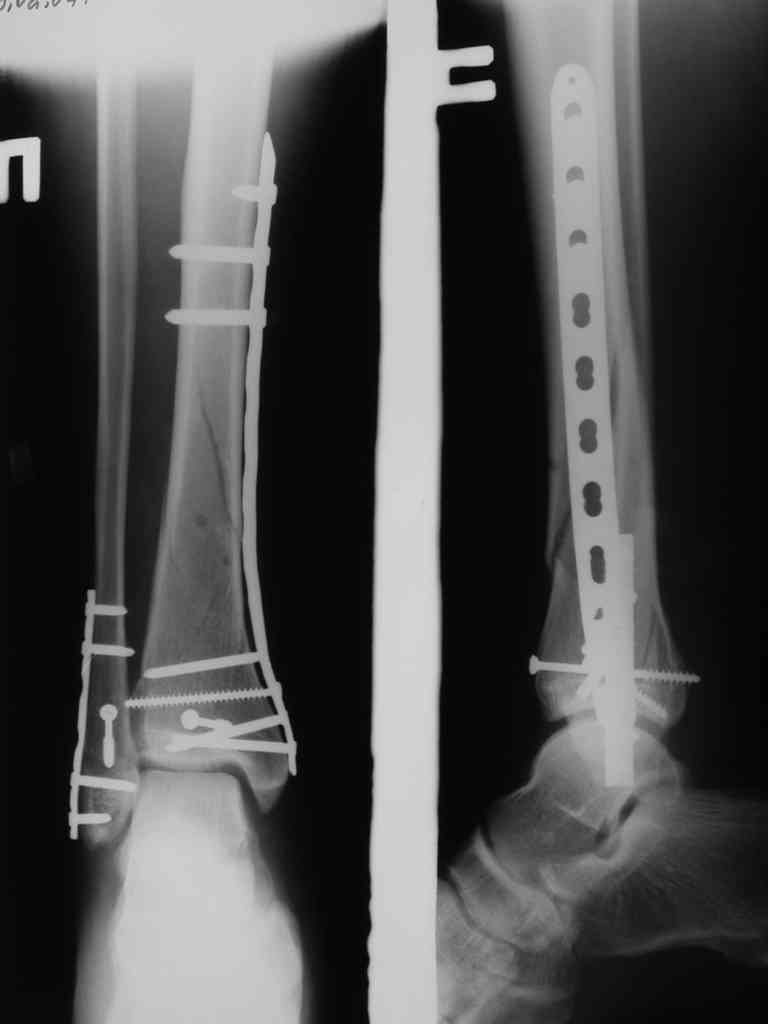

На фото простой суставной, метафиз. оскольчатый с переходом на диафиз перелом, пластина MIPO.

С Уважением А.Миронов